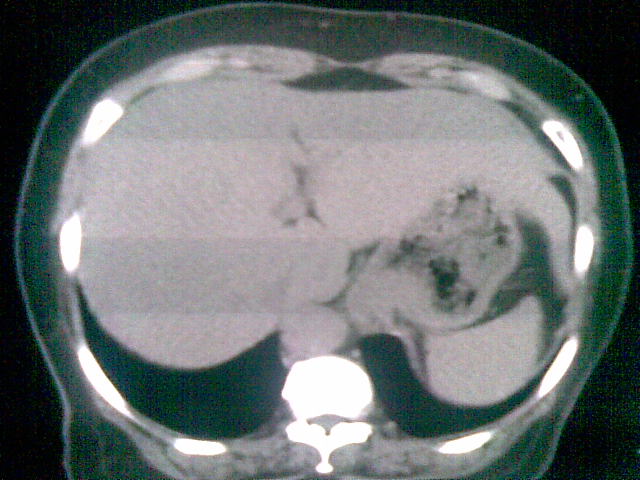

女 ,74岁,主诉食欲减退!上腹部痛,心慌!食管病变!请教ct会诊!

食管贲门出管壁局限增厚,结合胃镜确诊

胃底贲门癌累及食管下段